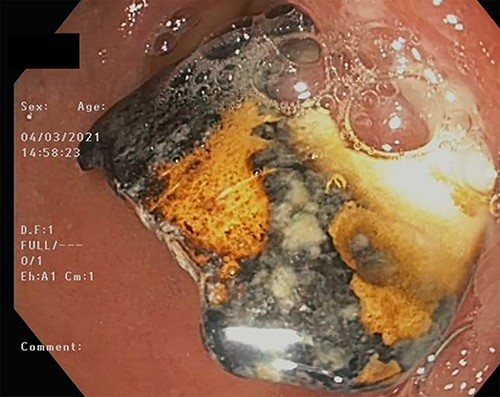

On Day 7, a repeat upper gastrointestinal endoscopy was performed. The FB remained in the first part of the duodenum which it had begun to erode through posteriorly (Fig. 7). The endoscopy was fitted with an overtube and with the help of a snare the embedded FB was successfully retrieved.